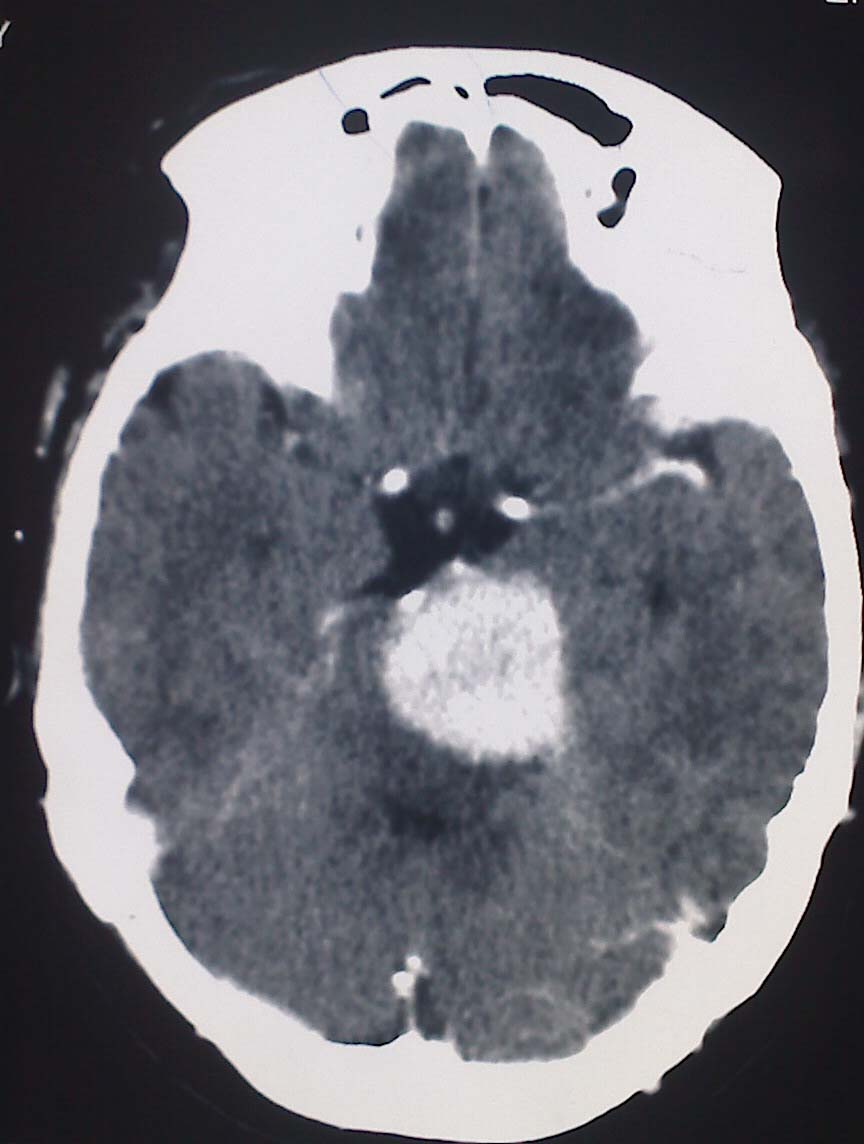

女性,56岁,查体所见,请会诊

平扫为较高密度,增强后病灶明显强化,边界清楚水肿不明显.考虑脑膜瘤.

左岩骨尖区脑膜瘤

从病变位置和强化表现看倾向脑膜瘤,但其跨越中后颅窝,也要结合临床,不能忽略三叉神经瘤,不过后者囊变较多。此病例的不足是无骨窗对照,脑膜瘤比较容易出现临近骨骼的异常。

左岩骨尖区占位病变,平扫呈高密度,病变跨中后颅窝生长,岩骨可见骨质吸收,周围未见明显水肿,增强扫描病灶明显强化。考虑左岩骨尖区脑膜瘤。

此片最大的缺憾是没骨窗,钙化及颅骨的改变不好看